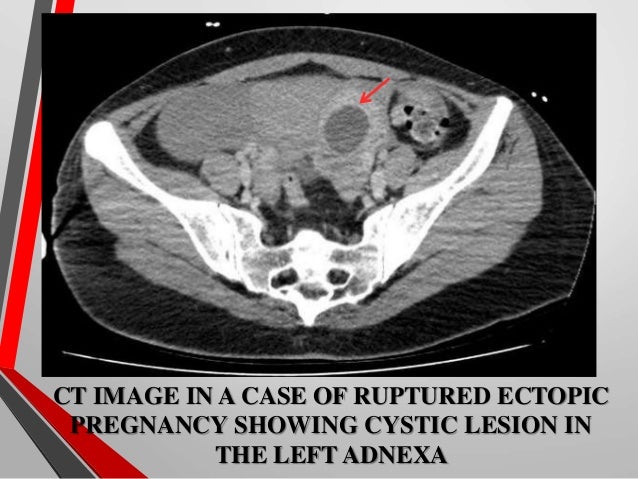

Ectopic Pregnancy Radiology | PPT

Ectopic pregnancy Radiology | PPT www.slideshare.net

Ectopic Pregnancy Radiology

Ectopic pregnancy Radiology www.slideshare.net

ectopic radiology